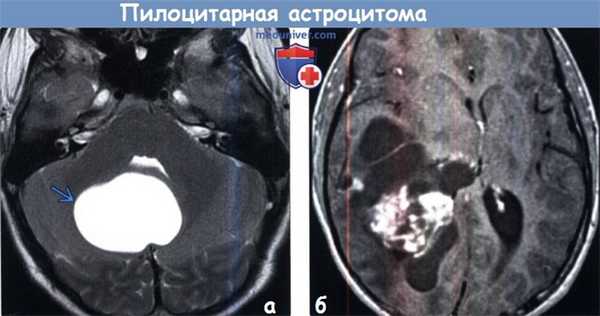

(а) МРТ, Т2-ВИ, аксиальный срез: у юноши с мозжечковой симптоматикой в задней черепной ямке определяется отграниченное гиперинтенсивное на Т2-ВИ объемное образование.

Отсутствие перифокального отека характерно для пилоцитарной астроцитомы. На постконтрастных изображениях определялось контрастирование пристеночного солидного компонента.

(б) МРТ, постконтрастное T1-BИ, аксиальный срез: у ребенка определяется крупное объемное образование, состоящее из кистозного и солидного компонентов.

Обратите внимание на масс-эффект, оказываемый образованием на окружающие структуры. Крупные размеры и гетерогенный характер контрастирования образования могут наводить на мысль о его более высокой степени злокачественности.

При резекции была выявлена пилоцитарная астроцитома (ПА) grade I.